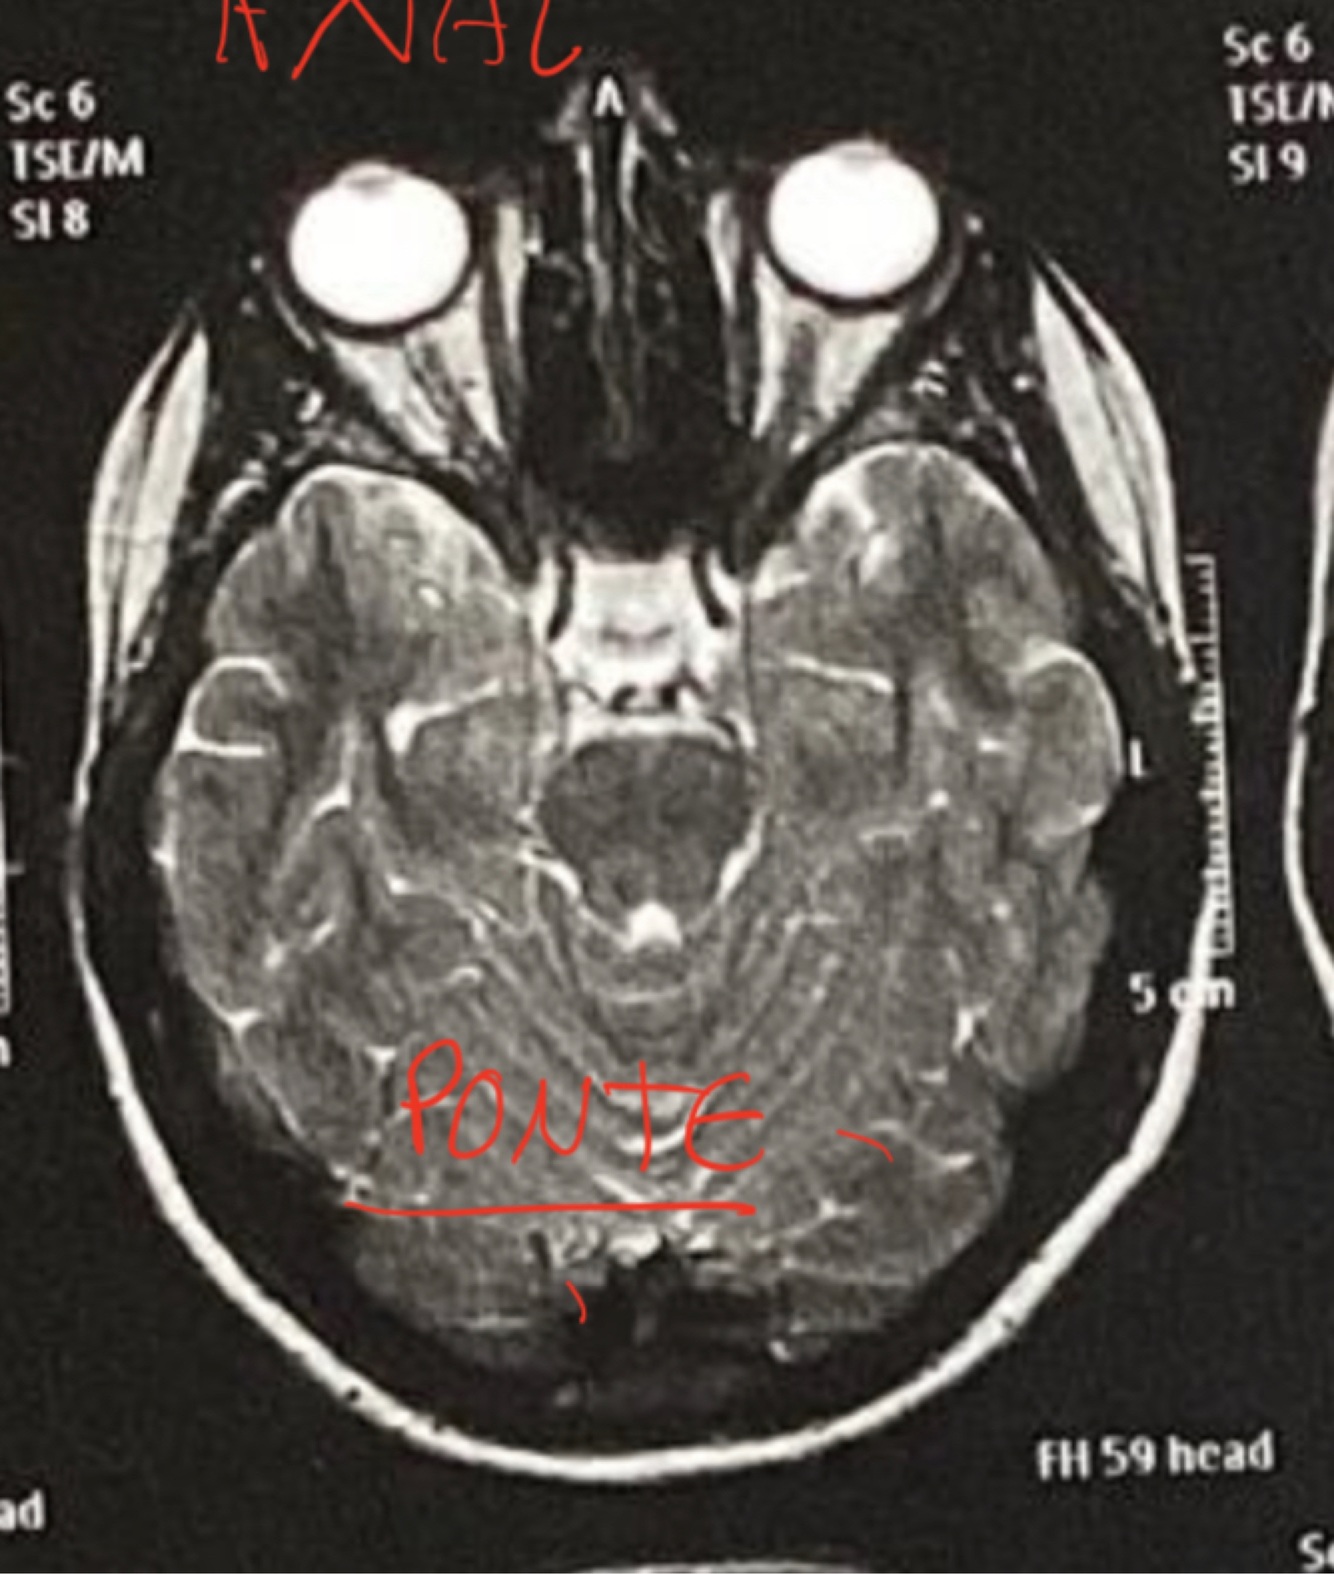

RM Axial Ponte

A

Dentinho